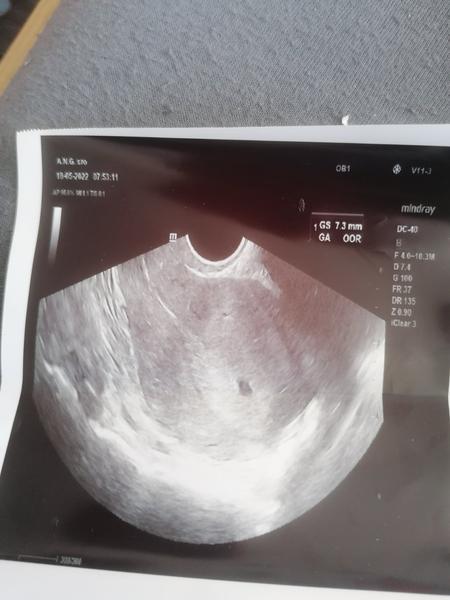

Ahojte dievcata idem sem s prosbou podelit sa o vasu skusenost dnes som bola na gynekológii ms mi meska 7 dni testy su pozit prilozim foto a na ultrazvuku bola vidiet iba tala mala gulicka 7.3mm odmerala doktorka zartja mi dojdu visledky z krci hcg mala ste taketo nieco aj vy na ultrazvuku malinke na 7 dni meskania ms a potom to dopaflo ok? Druhy termin mi dala az 2 juna dakujem pekne

@srdiecko99 Po meškaní 7 dní tam ešte moc nie je čo vidieť, keď ti dala termín takto, tak je zatiaľ všetko v poriadku. Inak by ti to dr už povedala. Držím palce 🙂

@srdiecko99 je to tam a je to ok

Na 7 dní meškania he to duper...niekedy není ešte vôbec nič vidieť....